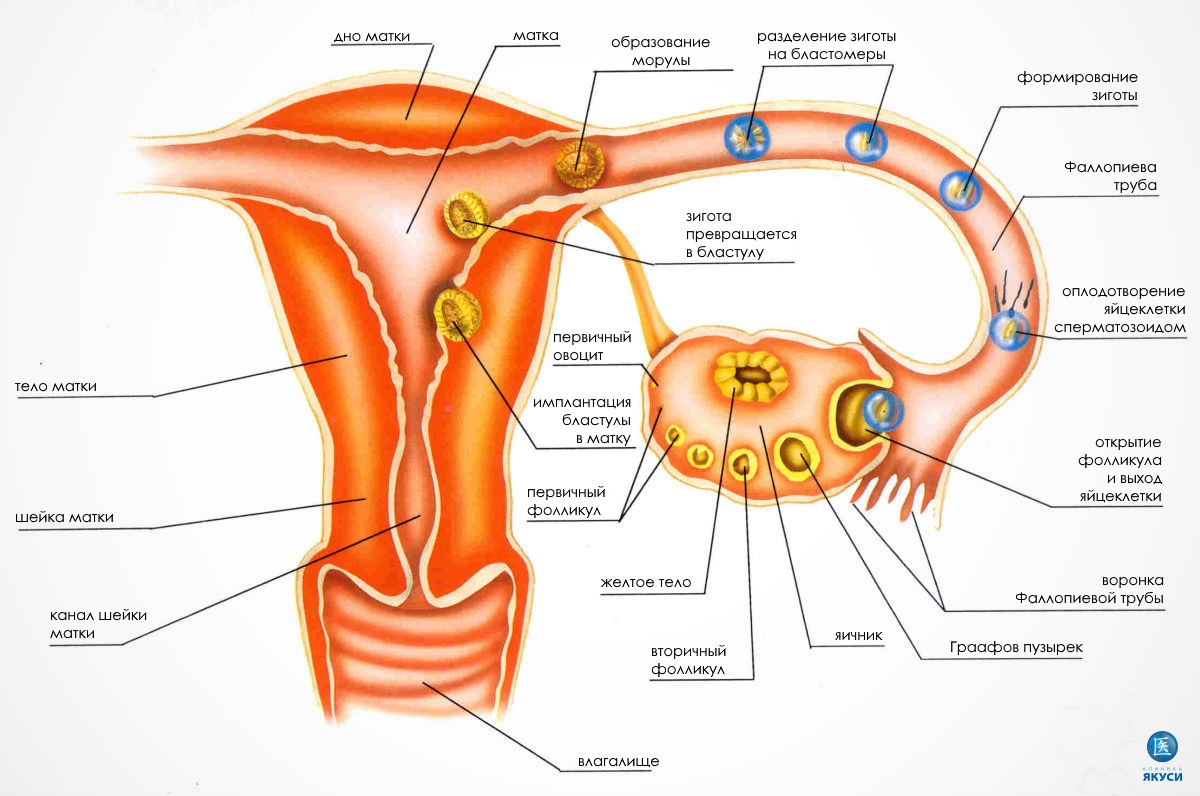

Созревание фолликула в яичнике: этапы и процессы

Раздел: Другие животные